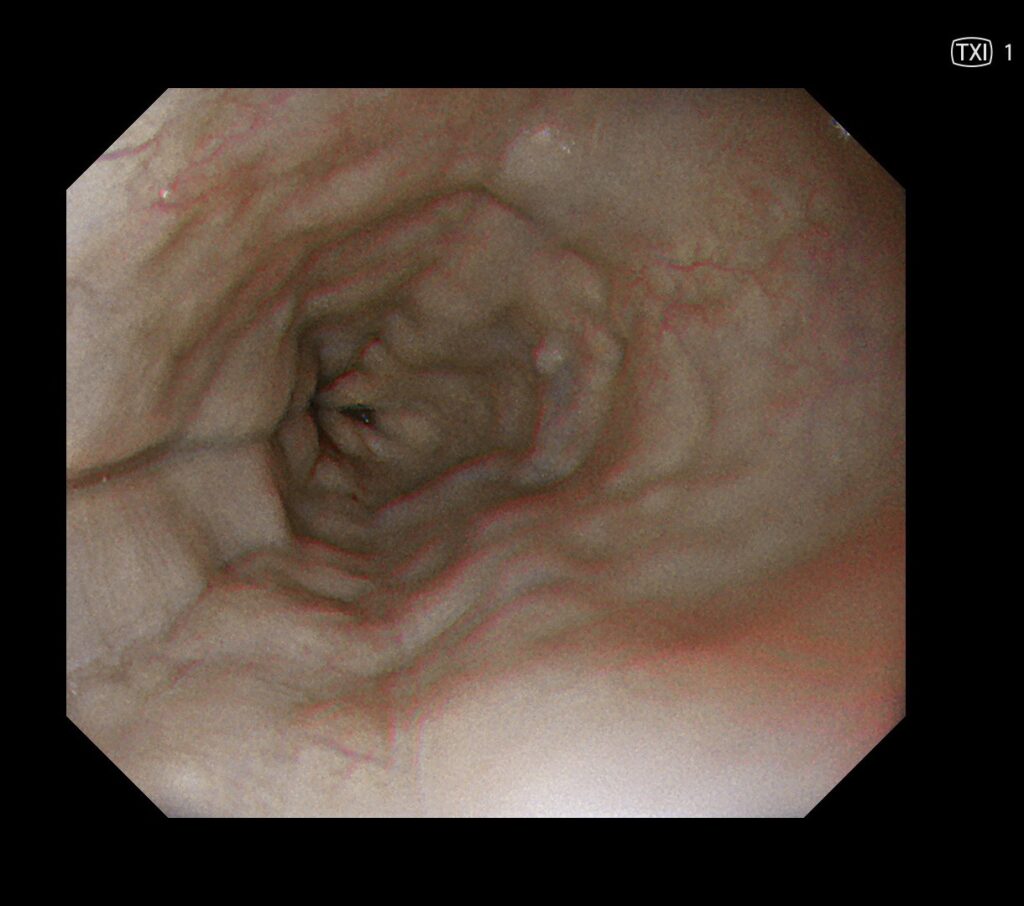

②TXI(特殊光観察)とは、以下のように、色調や凹凸を自動で強調してくれるモードです(最新のオリンパスの光源に導入された新しい観察モードです)。

※ちなみに画面真ん中に微小胃癌があります。

内視鏡的特徴は、以前の症例提示していますが、輪状ヒダ・縦走ヒダが特徴です。

これも、白色光観察で発見するより、TXIでヒダがより際立ちますので、輪状ひだや縦走ヒダが視認しやすくなる印象にあります。